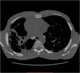

Progressive massive fibrosis (PMF), characterized by the development of large conglomerate masses of dense fibrosis (usually in the upper lung zones), can complicate silicosis and coal worker's pneumoconiosis. Conglomerate masses may also occur in other pneumoconioses, such as talcosis, berylliosis (CBD), kaolin pneumoconiosis, and pneumoconiosis from carbon compounds, such as carbon black, graphite, and oil shale. [Source: Wikipedia ]